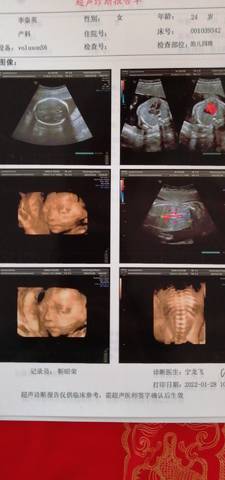

23周十4做四维,右心室强光斑。

东西没那么严重,目前主要是关注一下后面能不能吸收,包括有没有之前做无双检测。

一般情况没事